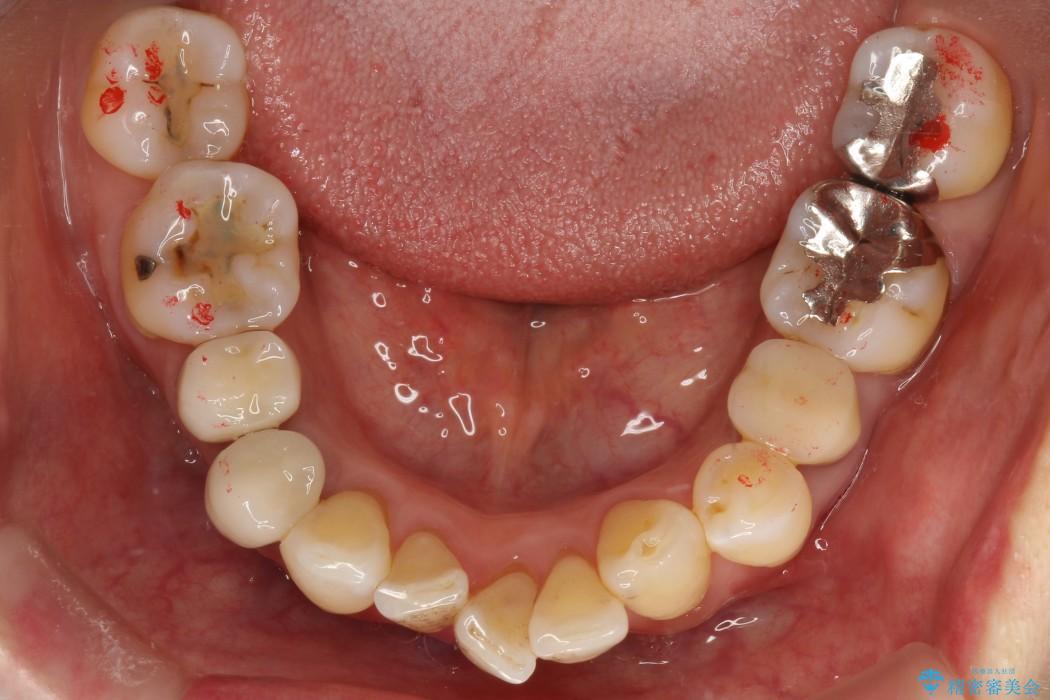

【50代女性】八重歯のインビザライン矯正 治療例

八重歯の改善を希望され来院されました。

当初はセラミックでの治療を希望されていましたが、噛み合わせと歯並びを治していく為に矯正治療を提案させていただき、インビザラインでの矯正を行う計画にしました。

頻繁にご来院いただく事が難しかったこともあり、型取りのし直し(リファインメント)を2回行いました。時間はかかってしまいましたが、患者様には大変ご満足していただくことができました。